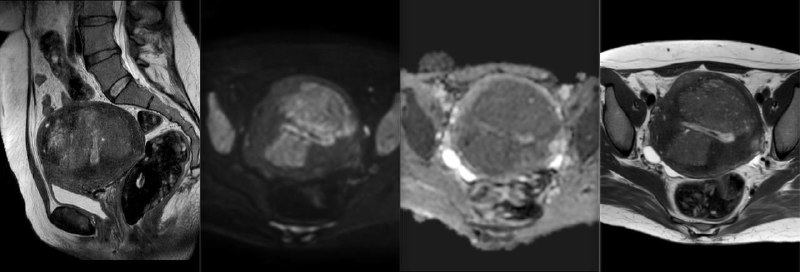

Очень интересные проявления в матке: видно, что имеется выраженный, диффузный аденомиоз, но какие-то узловые включения, ограничивающие диффузию и практически не накапливающие контраст. Это – результат перкутанной эмболизации, думали, что миом матки. Пациентка страдала маточным кровотечением.

Развившиеся после процедуры участки некроза в стенках матки находятся в состоянии цитотоксического отёка и не накапливают контраст. Без знания анамнеза угадать, что это, практически, невозможно, особенно при отсутствии соответствующего опыта. Снимки и прислали с вопросом: это что такое злое в матке, но не накапливает контраст? Хорошо, что анамнез сообщили.